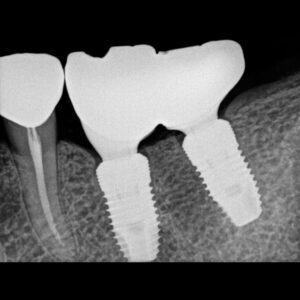

Exceptional image quality and robust durability intraoral–imaging device

Designed for precision and consistent performance, our intraoral sensor offers unparalleled comfort and quality. This long-lasting, reliable sensor is designed to withstand the daily stresses of dental practice.

The intraoral sensor that does it all

Our sensors are tailored to fit perfectly, further enhancing the patient’s comfort during the imaging process. Whether it’s a child or an adult, our sensors are designed to fit perfectly.